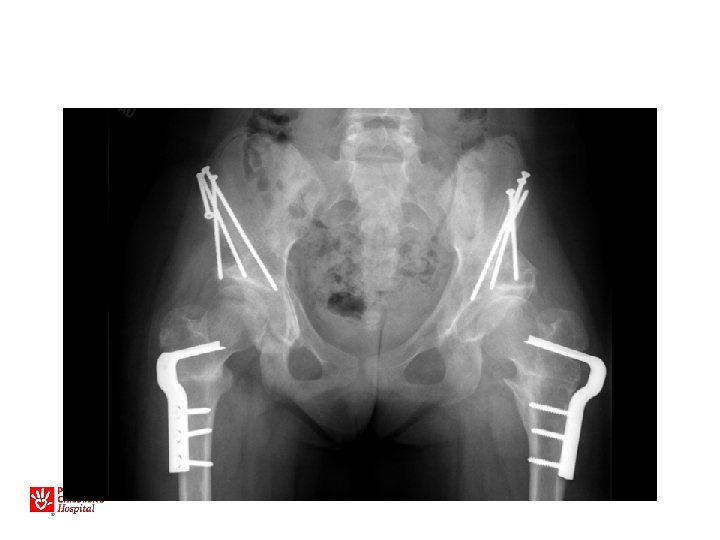

13 yo with hip pain, limp • Family has noted increased pain with activity, not able to walk long distances • No infantile treatment or history • Patient has features of Charcot-Marie. Tooth (associated with hip dysplasia)

• Bilateral periacetabular osteotomies • Bilateral femoral osteotomies